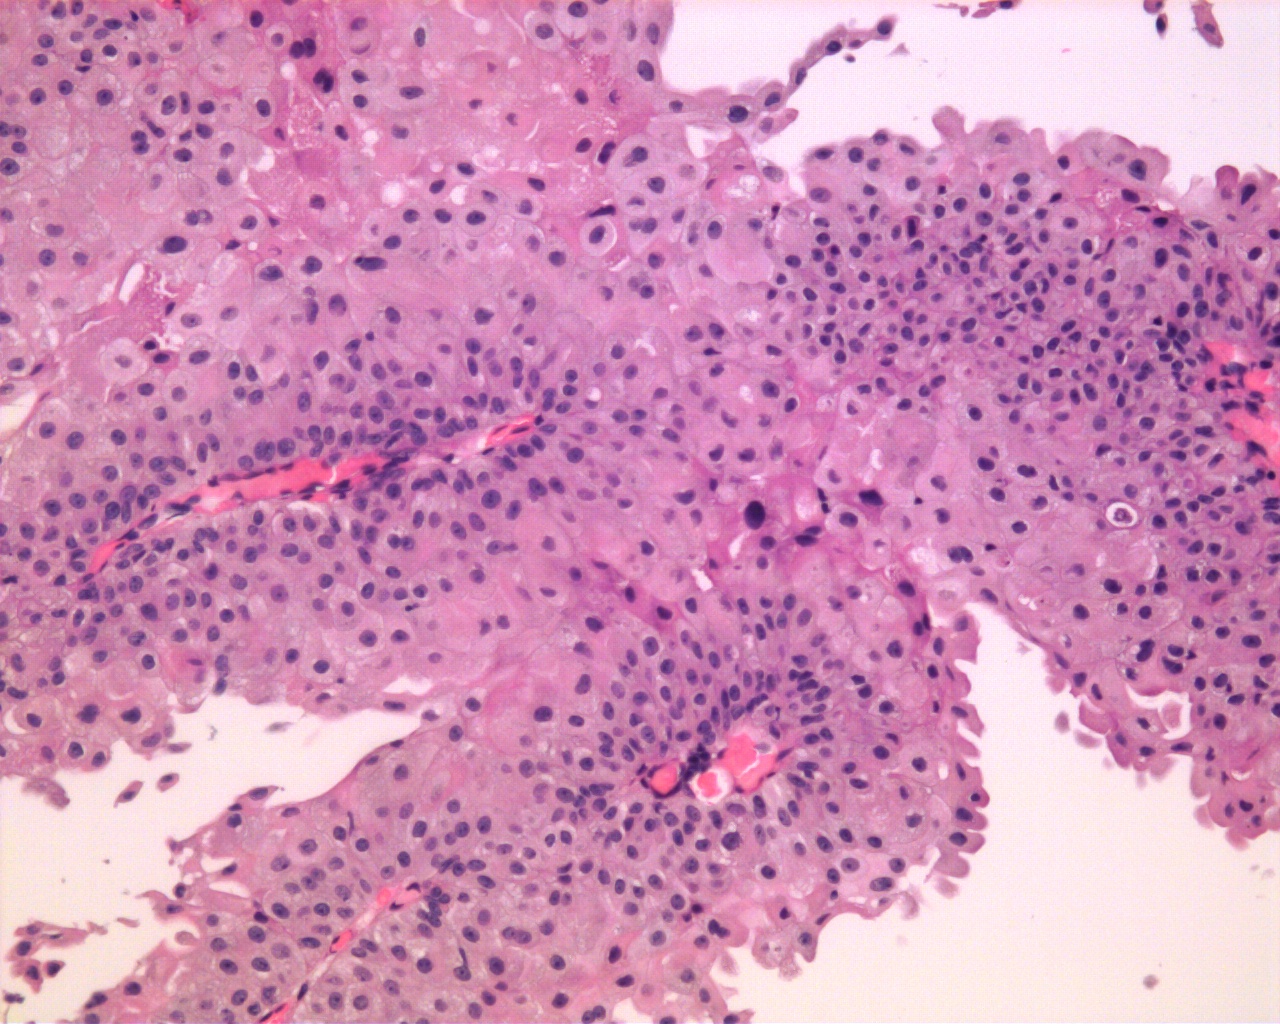

Bladder Papillary Lesions

Case ID: 592